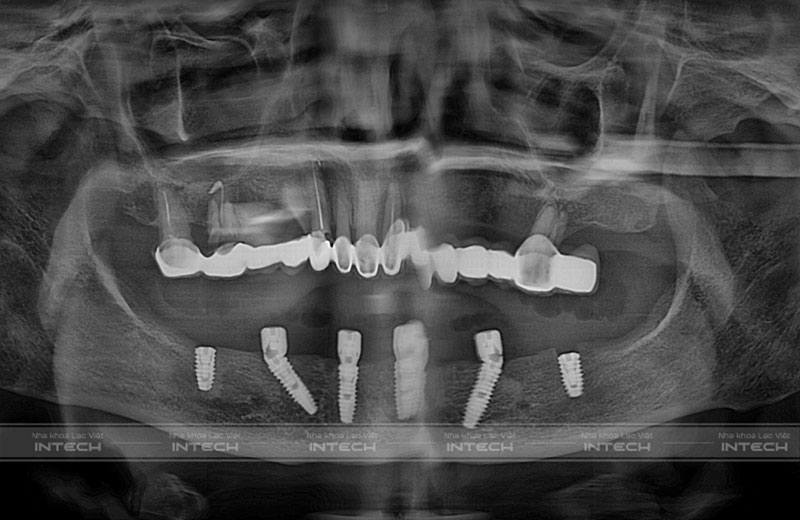

Dưới đây là phim CT Cone Beam của cô Chu Thị Sinh sau khi trồng răng Implant.

Phim CT Cone Beam của cô Chu Thị Sinh sau cấy Implant

Bác sĩ đã đặt tổng cộng 6 trụ Implant ở hàm dưới, trong đó có 2 trụ ở phía trước đặt thẳng, 2 trụ nghiêng ở 2 bên để tránh các mốc giải phẫu và 2 trụ đằng sau. Sau khi cấy ghép Implant, bác sĩ có lắp hàm tạm cho khách hàng để về nhà có thể ăn nhai thoải mái.